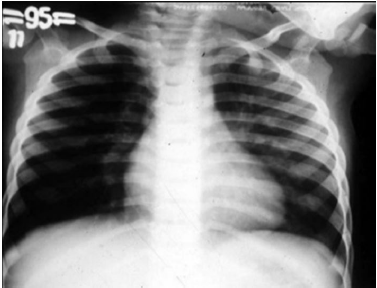

Um lactente de quatro meses de idade cronológica, nascido prematuro de vinte e nove semanas gestacionais, apresentou, durante o inverno, febre, tosse e dificuldade respiratória nos últimos três dias antes de ser levado por sua mãe à emergência pediátrica. A mãe relatou que a criança nunca havia apresentado um episódio semelhante a esse. O calendário vacinal mostrou que a criança recebeu duas doses da vacina antipneumocócica decavalente, porém não recebeu palivizumabe. O exame físico da criança mostrou desidratação, taquipnéia, retração intercostal e sibilos inspiratórios e expiratórios. O resultado do hemograma solicitado pelo médico revelou hematócrito de 40%, concentração de hemoglobina de 13 g/dL, 9.000 leucócitos/mm3, 55% de linfócitos, 34% de neutrófilos, 2% de eosinófilos, 1% de basófilos, 8% de monócitos, 340.000 plaquetas/mm3. O médico solicitou radiografia de tórax da criança, cuja imagem é apresentada na figura.

Nesse caso, a pneumonia bacteriana não configura um diagnóstico diferencial, pois se trata do primeiro episódio de dificuldade respiratória com broncoespasmo. Além disso, a radiografia do tórax não mostra áreas de atelectasia ou condensação.